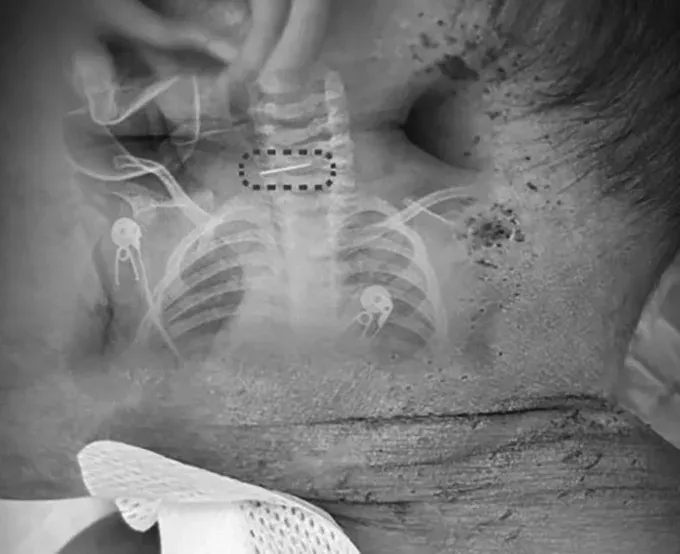

นายแพทย์สุย เหวิน หยวน แพทย์จากศูนย์โรคกระดูกสันหลัง โรงพยาบาลซินหัว สังกัดมหาวิทยาลัยแพทยศาสตร์เจียวทง มหานครเซี่ยงไฮ้ เปิดเผยว่า เด็กถูกส่งตัวมารักษาด้วยอาการไข้สูง และตรวจพบรอยเข็มแทงกระจายตั้งแต่ศีรษะ ลำตัว ไปจนถึงแขนขา หลายจุดเริ่มตกสะเก็ดสีดำ บ่งชี้ว่าเกิดขึ้นมาแล้วระยะหนึ่ง

ที่น่าตกใจคือ แพทย์พบเข็มเย็บรองเท้าที่หักเป็น 2 ท่อน ฝังลึกอยู่บริเวณกระดูกสันหลังส่วนคอของเด็ก จำเป็นต้องผ่าตัดฉุกเฉินทันที เนื่องจากตำแหน่งดังกล่าวอยู่ใกล้หลอดเลือดแดงคาโรติด ซึ่งหากเกิดความผิดพลาดเพียงเล็กน้อย อาจทำให้เด็กเสียชีวิตได้

แพทย์ระบุว่าการผ่าตัดครั้งนี้มีความซับซ้อนอย่างมาก เพราะกระดูกสันหลังส่วนคอของทารกวัย 10 เดือนยังพัฒนาไม่สมบูรณ์และเปราะบางสูง อีกทั้งเข็มเย็บรองเท้ามักมีเงี่ยงที่ปลาย หากดึงออกไม่ถูกวิธี อาจเกี่ยวเนื้อเยื่ออ่อนและก่อให้เกิดการบาดเจ็บรุนแรงได้

โชคดีที่การผ่าตัดนำเข็มที่ขึ้นสนิมออกประสบความสำเร็จ เด็กมีอาการดีขึ้นอย่างต่อเนื่อง หลังเข้ารับการรักษา 4 วัน อาการไข้ลดลงและสามารถย้ายออกจากหอผู้ป่วยวิกฤตได้ในเวลาต่อมา